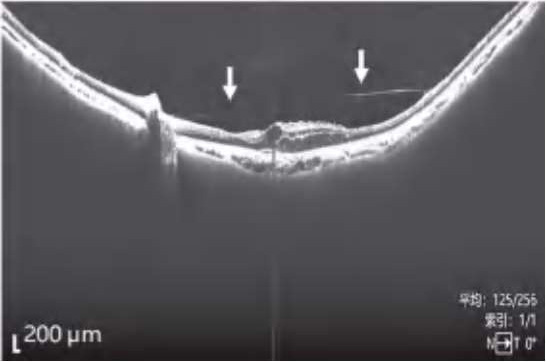

图2-2-1 抗VEGF及PRP治疗后玻璃体后脱离范围显著扩大的PDR案例

A.PDR合并玻璃体视网膜牵拉引发的相关DME,既往已行PRP,行4次抗VEGF药物治疗后,黄斑区玻璃体后界膜与视网膜分离(白色箭头所示),玻璃体视网膜牵拉解除,黄斑水肿较前明显好转。B.PDR合并玻璃体视网膜牵拉性相关DME,在行3次视网膜激光光凝治疗后,黄斑区玻璃体后界膜与视网膜分离(白色箭头所示),玻璃体视网膜牵拉缓解,黄斑水肿较前好转。